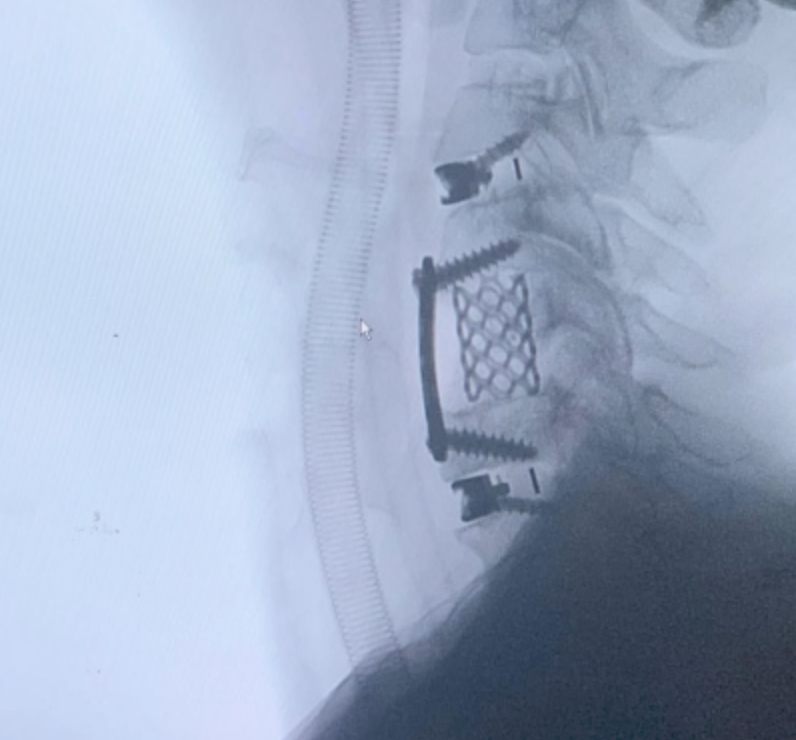

CIRUGIAS

RESULTADOS